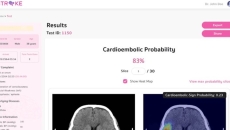

Also, Omron Healthcare India is launching a remote heart health management platform with AI company Tricog.

They will deploy AI to help reduce delays and gaps in stroke care management.